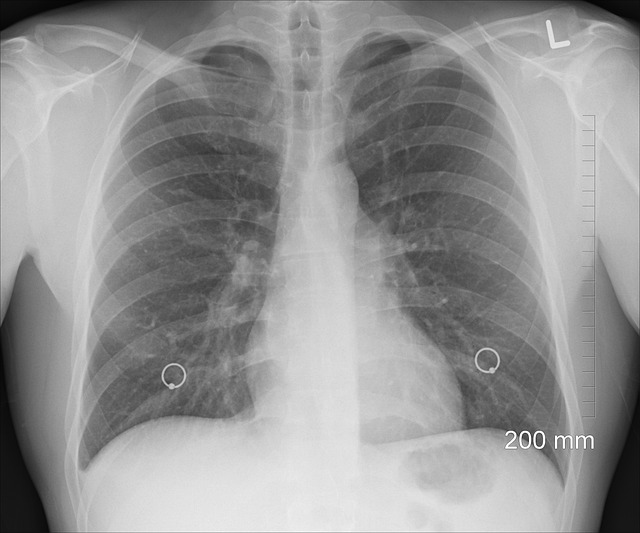

폐렴의 이야기는 수세기에 걸쳐 의료 역사의 일부로 남아 있습니다. 그러나 폐렴과 그 원인 요소에 대한 현대적인 이해는 미생물학의 중요한 발견과 의료 영상 기술의 발전과 함께 19세기와 20세기에 조금씩 나타나기 시작했습니다. 루이 파스퇴르의 개척적인 업적부터 비로엔트로엔트겐이 새겨진 흉부 방사선술의 등장까지, 각 이정표는 폐렴의 병리학적 메커니즘과 치료 방법을 더 깊게 이해할 수 있도록 발판을 마련했습니다. 폐렴은 다양한 증상 스펙트럼을 통해 다양한 증상을 보이며, 이로 인해 진단에 어려움을 겪고 있습니다. 기침, 발열, 흉통, 호흡곤란 및 피로감은 대표적인 증상이지만, 기저 원인 요인, 환자의 인구 통계학적 특성 및 동반 질환에 따라 발현이 다를 수 있습니다. 증상의 서서히 나타나는 특성은 일반적인 호흡기 감염과 유사하게 나타날 수 있으므로 증상을 제때 인식하고 적절한 치료 전략을 시작하기 위해 높은 수준의 임상 의심이 필요합니다. 또한 폐렴의 빠른 진행성은 미세한 임상 징후를 인식하고 적절한 관리 전략을 취하는 것이 중요함을 강조합니다. 폐렴을 진단하기 위해서는 임상 평가, 방사선 영상 및 실험실 조사를 포함한 종합적인 평가가 필요합니다. 청진 이상 및 생명 체질량 지수 변화와 같은 임상 소견은 초기 단계에서 중요한 힌트를 제공하여 후속 진단 단계를 안내합니다. 폐렴 진단에서 흉부 방사선은 감염을 나타내는 융합성 폐 변화를 감지하는 데 중요한 역할을 하며, 어려운 증례의 경우 컴퓨터 단층 촬영(CT)과 같은 고급 영상 기술은 질병의 심각성과 합병증 요인에 대한 추가 통찰력을 제공할 수 있습니다. 분비물 배양, 혈액 배양 및 호흡기 병원균 패널과 같은 실험실 검사는 원인 균을 확인하여 표적 항생제 치료를 실시하고 환자 결과를 최적화하기 위한 중요한 역할을 합니다.